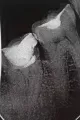

За день до события ел довольно твердые орехи, миндаль, 1 штуку (потом решил запить водой), но после них вечером и утром ел салаты, как обычно, и все нормально. После того как утром ел тонкий бездрожжевой армянский лаваш, который за 1 день стал немного черствым (корочка чуть тверже чем чипсы), в момент надкусывания дальними зубами услышал хруст и совсем небольшой кусочек зуба обнаружил в еде. По не понятной пока причине появилась трещина стенки 7-го зуба со стороны языка в четверти стенки, которая ближе к горлу. Видно, что есть трещина и в месте трещины есть небольшое углубление цвета кофейного налета (предположительно оттуда и выпал кусочек).

Стеночка еще держится, но упирается в десну и шатается.

Можно ли ее как-то шунтировать, прозрачной шунтирующей лентой, чтобы она приросла обратно? Или ее потребуется извлекать и реставрировать зуб, изготавливая пломбу? Во сколько это примерно обойдется? Снимок на телефон ничего не даст, а рентген не делали.

Стенку зуба, конечно, необходимо только удалить, а восстановить коронковую часть зуба теперь можно будет только вкладкой и коронкой.